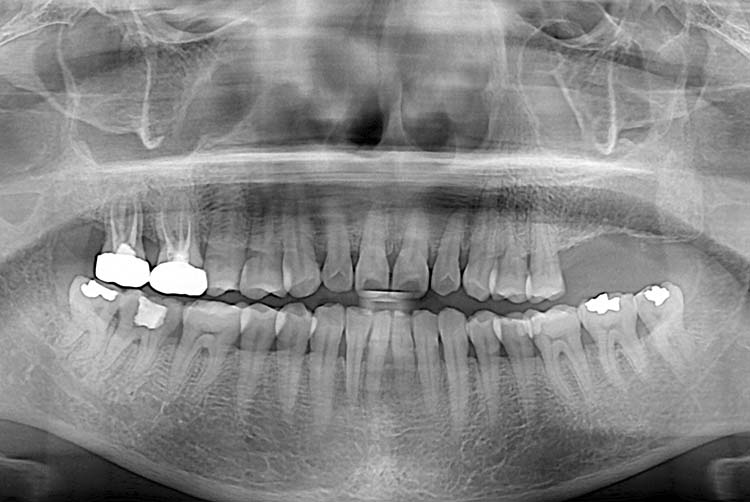

치료전 : 2015-04-01

세종치과는 많은 환자와 다양한 케이스를 바탕으로 항상 편안한 임플란트 수술을 제공하고자 노력하고,

오래동안 튼튼히 쓸 수 있는 임플란트 수술을 가장 큰 목표로 삼고 있습니다.